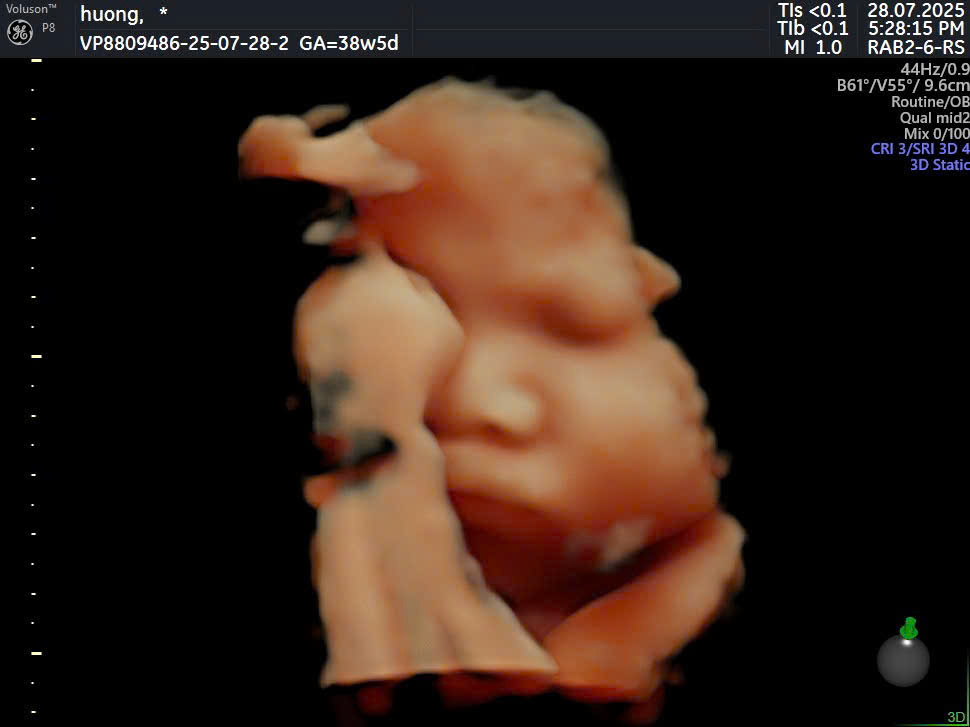

Công nghệ siêu âm 2D, 3D, 4D giúp theo dõi quá trình phát triển của thai nhi một cách toàn diện. Nhờ đó, bác sĩ có thể phát hiện sớm các dấu hiệu bất thường để can thiệp kịp thời, giúp quá trình sinh đẻ diễn ra an toàn hơn.

Phòng khám được trang bị máy móc siêu âm, xét nghiệm và phòng sinh đạt chuẩn quốc tế. Điều này giúp nâng cao độ chính xác trong chẩn đoán và đảm bảo an toàn trong quá trình sinh đẻ.